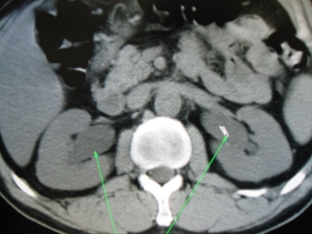

Instrumental methods for diagnosing Ormond's disease

The following instrumental methods are used to diagnose Ormond's disease:

- excretory urography: allows you to determine the expansion of the pyelocaliceal system of the kidney and ureter to the level of its compression, the displacement of the ureter towards the spine;

- antegrade pyeloureterography is performed if excretory urography is contraindicated or renal function is severely reduced;

- radionuclide diagnostic methods allow to determine the anatomical and functional state of the kidneys;

- Computer and magnetic resonance imaging makes it possible to clarify the boundaries of the lesion.